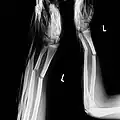

- Schraubenosteosynthese am Beispiel einer Fraktur des Capitulum humeri

-

Eine „Meißelfraktur“ der speichenseitigen Gelenkrolle des Oberarms -

Das Capitulum ist um etwa 90° verkippt -

Nach exakter Reposition ist der Bruchspalt kaum noch erkennbar -

Die Schraube komprimiert den Bruchspalt, der zusätzliche Draht verhindert lediglich die Rotation des Fragments